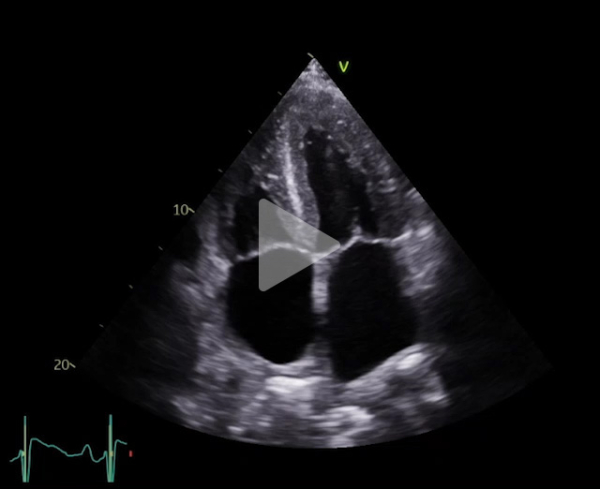

Vidéo 2

Vidéo 3

FEVG 40% en Simpson biplan, 45-50% visuellement. GLS -7%. Hypokinésie des bases et hyperkinésie de l'apex. VG non dilaté (DTDVG = 35mm, VTDVG =54ml/m2), hypertrophié (SIV = 18.5mm, PPVG = 19mm).

- DC = 3l/min, IC = 1.6l/min/m2 avec CCVG = 21mm et ITV sous Ao = 8cm

- OG dilatée à 40mL/m² (21cm2). OD dilatée à 19cm2

- Cavités droites non dilatées (Anneau tric =35mm)

- Fonction VD altérée (TAPSE = 7.7mm, S tric = 5.9cm/s)

- PAPS estimée sur IT modérée à 30 + 15mmHg (TAP 82ms)

- VCI dilatée ( 22mm), non compliante

- Lame péricardique minime